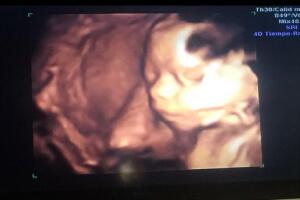

En más de una ocasión presumió el ultrasonido de su bebita: "Mi 2016 💜✨🦄 #teestamosesperando #Lúa #venga2017".